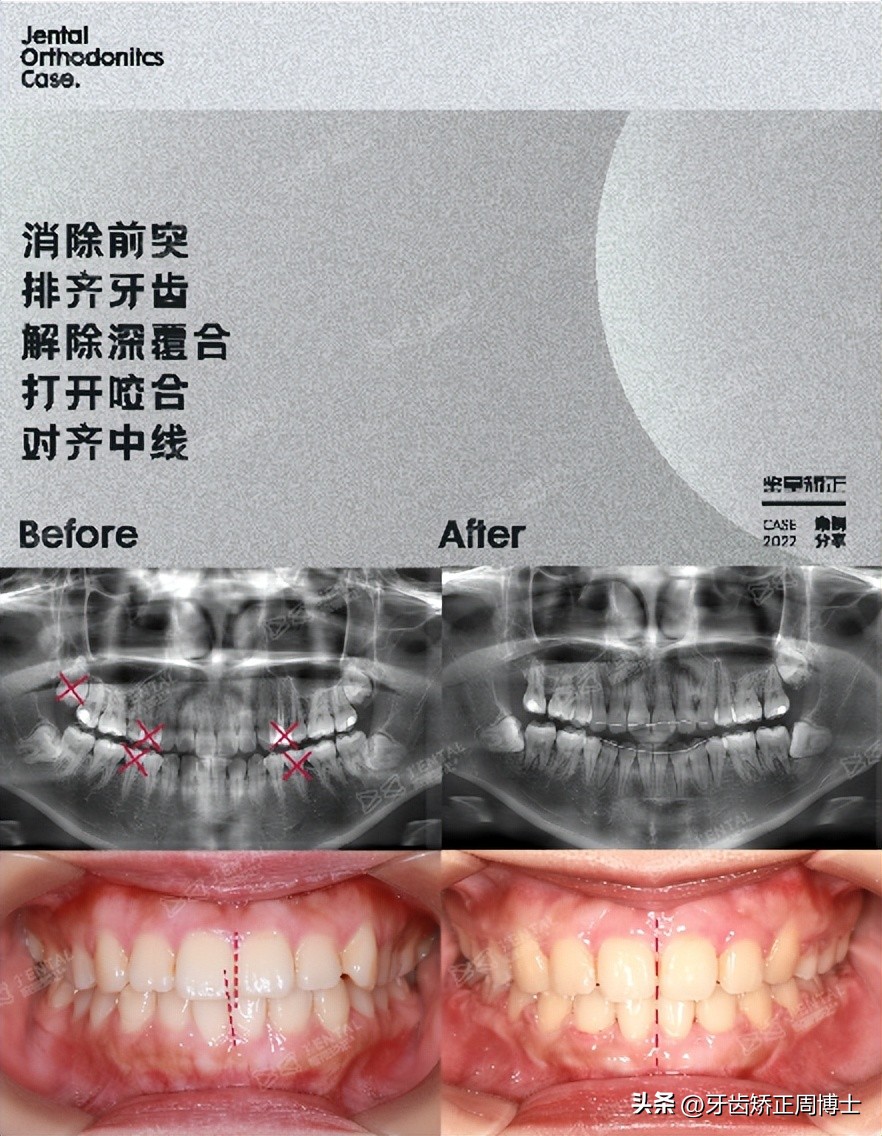

初诊情况来看,她上下牙列比较拥挤,前突2度,后缩2度。从侧位片上可以看到,她属于高角面型,下颌骨条件是不错的。作为先天条件好的案例,我们只需要正确的雕琢,就能完美展现。

拔除4颗正畸牙,利用拔牙的空间,并借助6颗支抗钉作垂直向的控制,内收前突,对前牙后牙同时进行压低,实现颌平面的逆旋。历时2年,骨性前突完美解决,下巴发生逆时针旋转,解除下巴后缩的问题。从侧面对比图看,女生最终达到了完美的直面型。